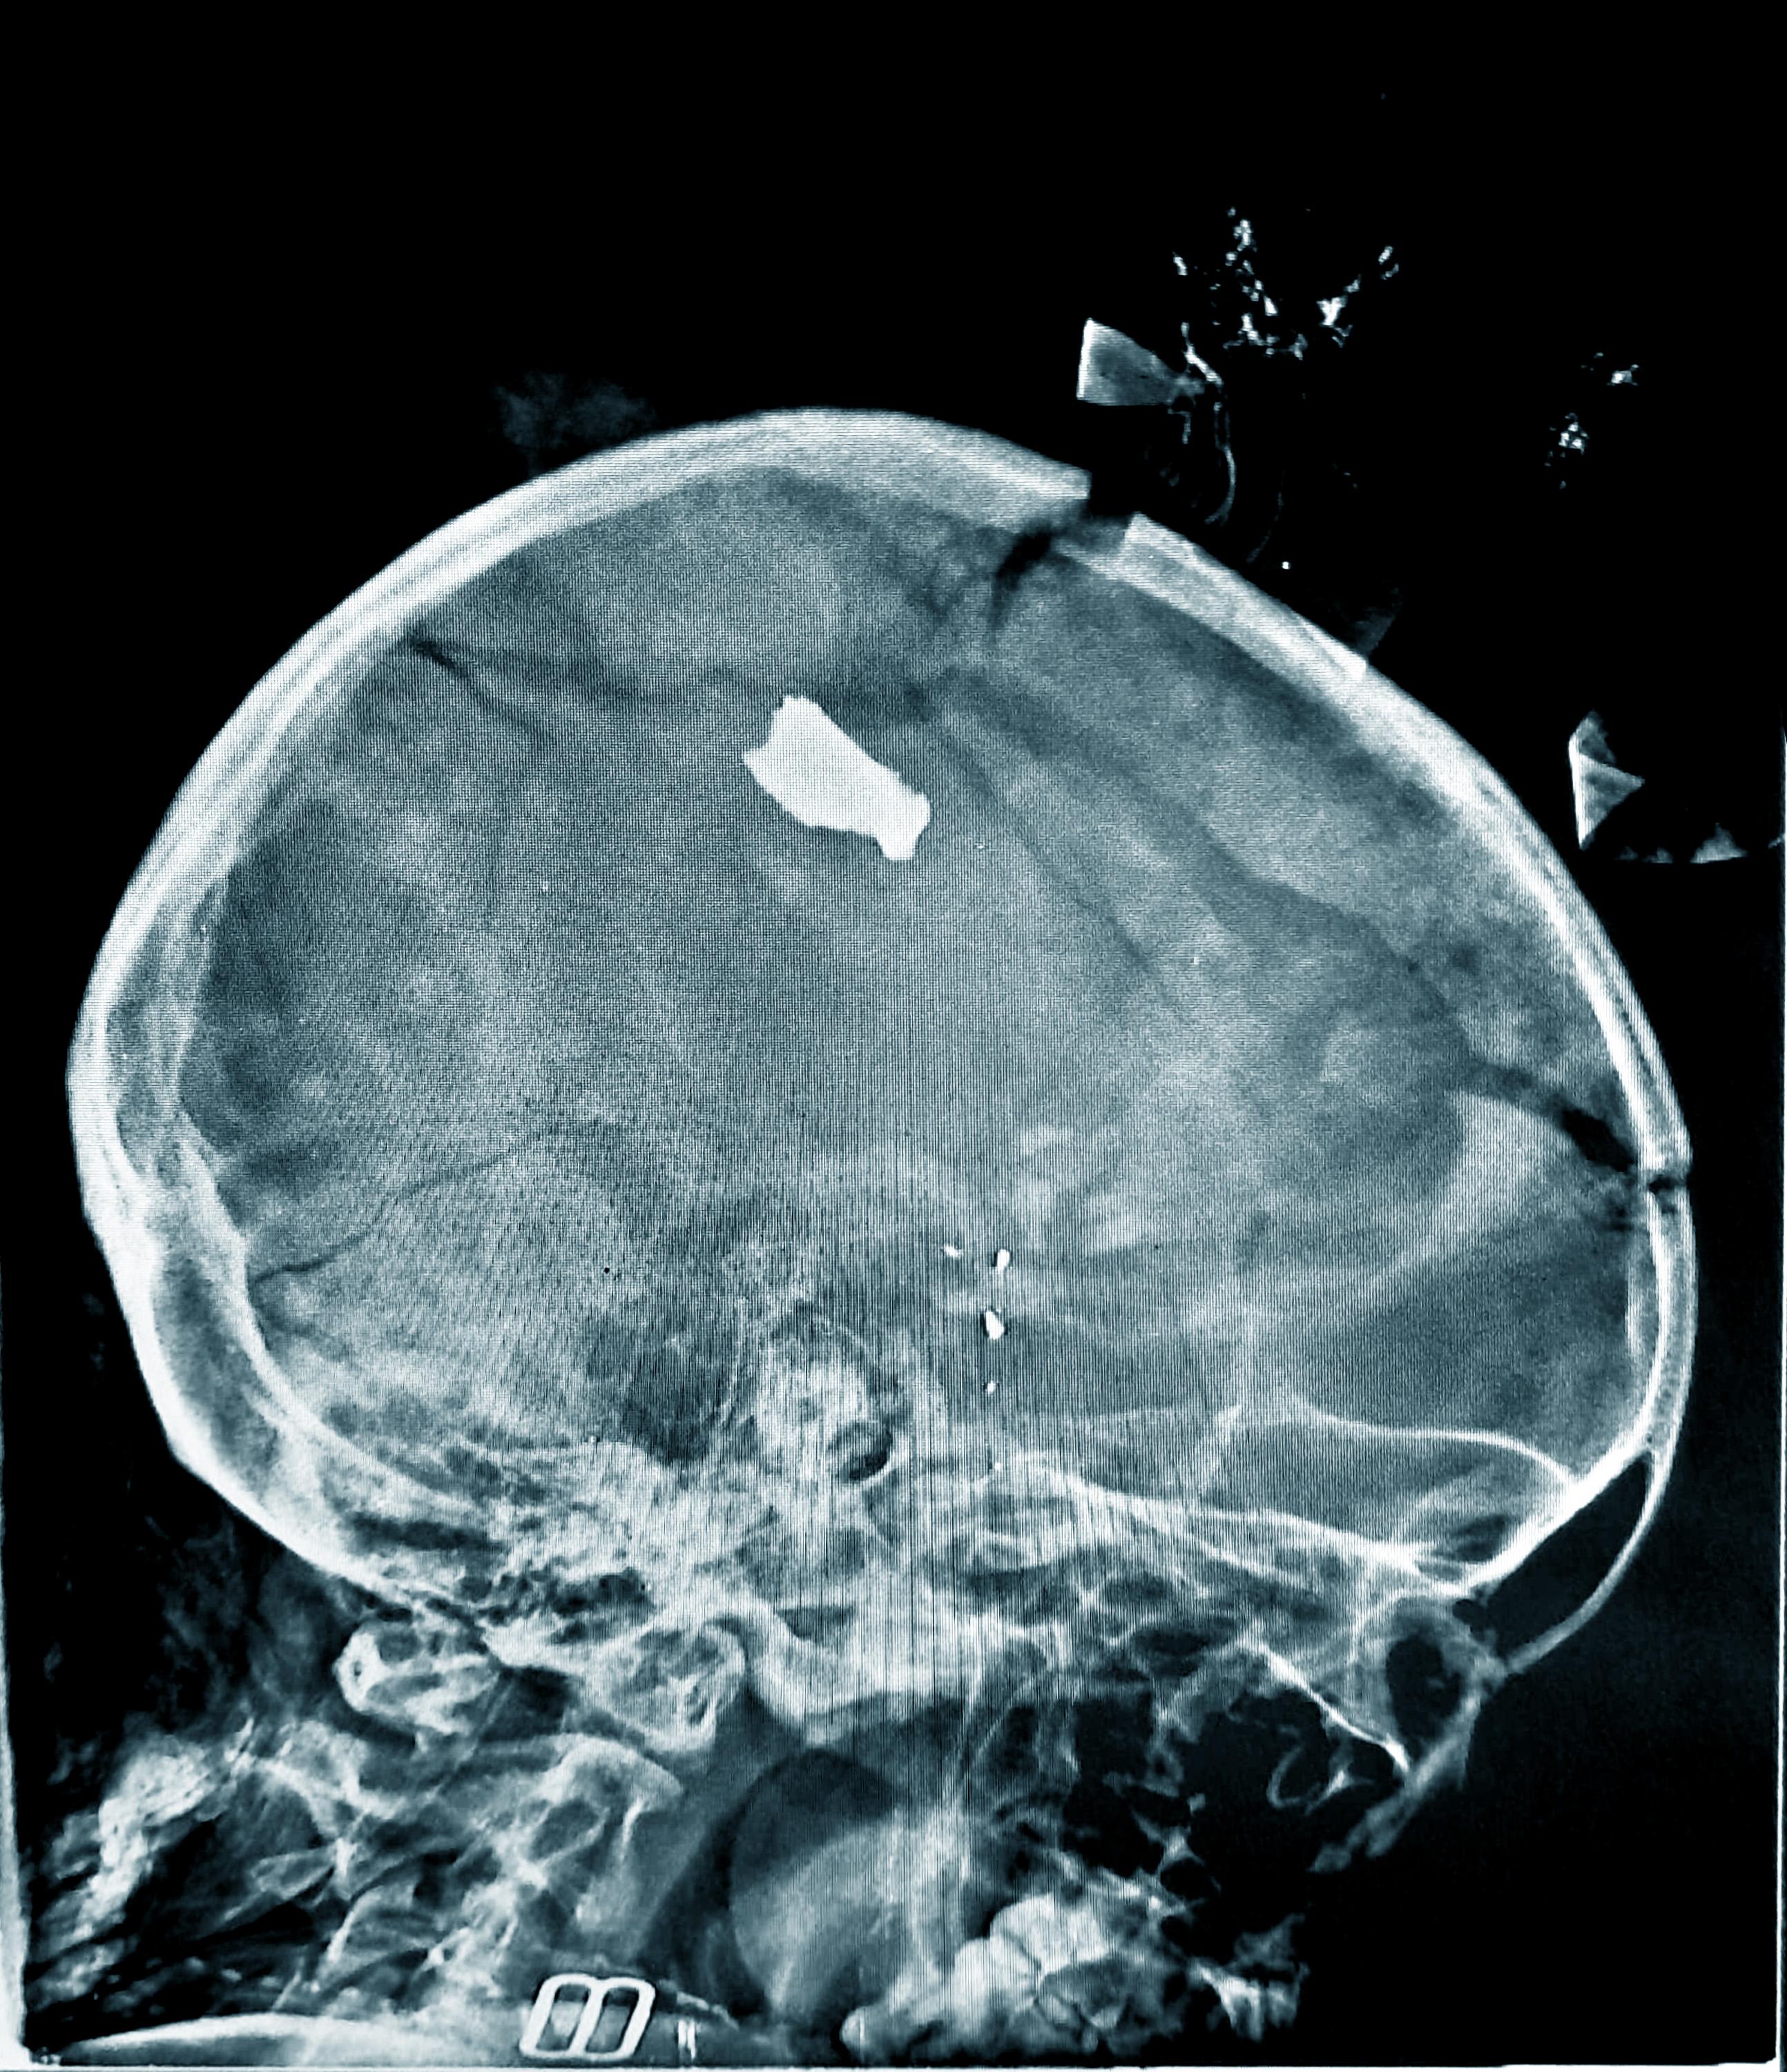

North Khartoum (Bahri), Omdurman, and south Khartoum were all affected by ground fighting, shelling, and air and drone strikes, resulting in large influxes of wounded patients at the Turkish hospital and Bashair Teaching hospital in south Khartoum, and at Al Nao hospital in Omdurman, where our teams worked. One in six war-wounded patients treated at Bashair hospital between January and November was under the age of 15.